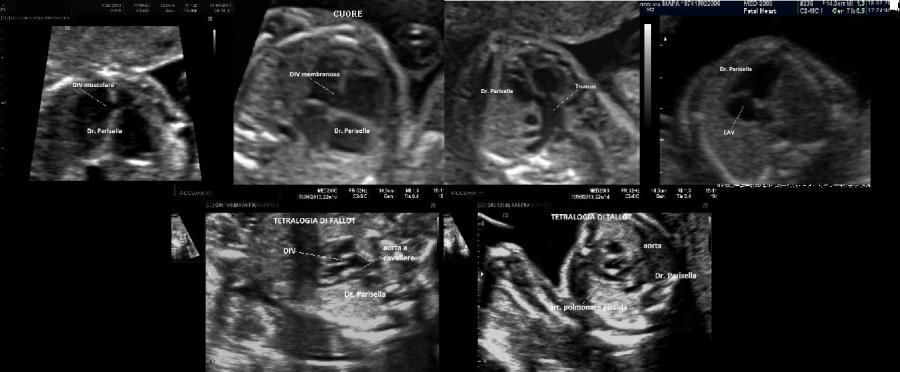

cardiopatie congenite